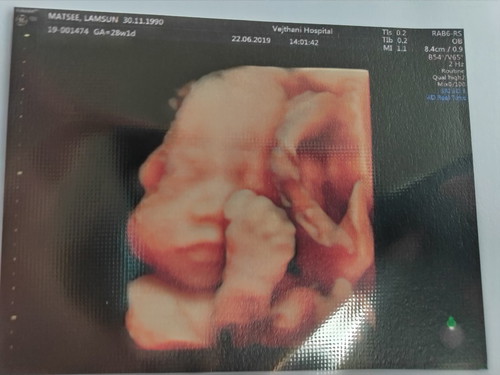

น้องหนักเท่าไหร่กันบ้างคะ บ้านนี้หนัก 1,193 กรัมแล้ว น้ำหนักแม่ขึ้นมา5กิโล ท้อง28w

อยากถ่ายภาพแบบนี้บ้างค่ะอันเตอรซาวแบบนี้เรียกว่า4มิติไช่เปล่าค่ะ

2มิตินะแม่